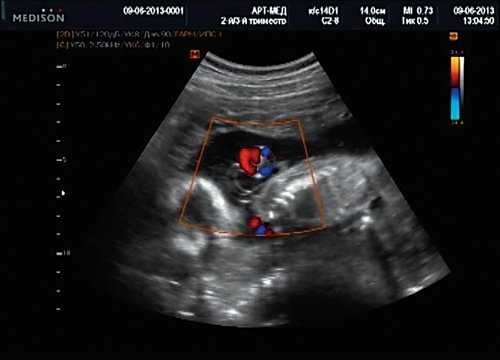

При эхокардиографии изучались четырехкамерный срез сердца плода (рис. 1) и срез через три сосуда (рис. 2). УЗИ проводилось трансабдоминальным датчиком, лишь при необходимости (затрудненная визуализация) использовался внутриполостной датчик. Четырехкамерный срез сердца плода при ультразвуковом сканировании трансабдоминальным датчиком визуализировался в 85% случаев, срез через сосуды - в 73%, при использовании трансвагинального датчика эти цифры существенно возрастали до 100 и 91% соответственно. Оптимизация пренатальной диагностики ВПС может быть достигнута путем строгого соблюдения основных методических правил. При оценке четырехкамерного среза плода необходимо оценить нормальное расположение сердца плода, исключив его эктопию (рис. 3), положение оси сердца плода, что не представляет никаких трудностей, нормальные пропорции и размеры камер сердца, движение створок атриовентрикулярных клапанов должно быть свободным, септальная створка трикуспидального клапана должна располагаться ближе к верхушке сердца (рис. 4). При оценке среза через три сосуда необходимо оценить взаиморасположение сосудов и их диаметр.

Беременная М., 21 года. Впервые обратилась в клинику в срок 20 нед беременности. Исследование проводилось на аппарате SonoAce-R7 (Samsung Medison) с использованием режима поверхностной объемной реконструкции 3D/4D. При изучении позвоночника плода в трех плоскостях костных деформаций не выявлено. В грудном отделе позвоночника обнаружено тонкостенное кистозное образование с анэхогенным содержимым, стебельчатой формы (рис. 10-12). Степень "прозрачности" содержимого была выше околоплодных вод, что позволяло идентифицировать его как ликвор. В проекции грыжевого выпячивания располагалась петля пуповины, дифференциальную диагностику которой без труда удалось провести с помощью ЦДК (рис. 13).